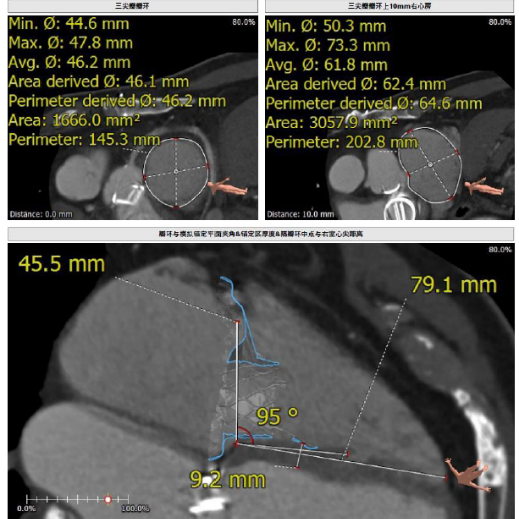

接受本次治療的是一例三尖瓣重度反流的患者,NYHA心功能Ⅲ級。主訴“反復活動后氣促1年,下肢水腫4個月”。入院N末端B型腦鈉肽前體(NT-proBNP)3161pg/ml。心電圖提示:心房顫動,ST-T改變。術前超聲提示:重度三尖瓣關閉不全,右心房擴大,三尖瓣收縮期位移(TAPSE)14mm,左房增大,左室收縮功能正常低值,主動脈瓣、二尖瓣機械瓣功能良好。術前CT評估(圖1):三尖瓣瓣環(huán)(周長換算直徑)大小為46.2mm;入路血管無嚴重迂曲,無鈣化;雙側冠脈有鈣化。